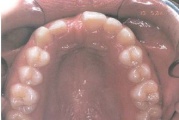

Suulaepoolt lõikunud koonilise kujuga lisahammas